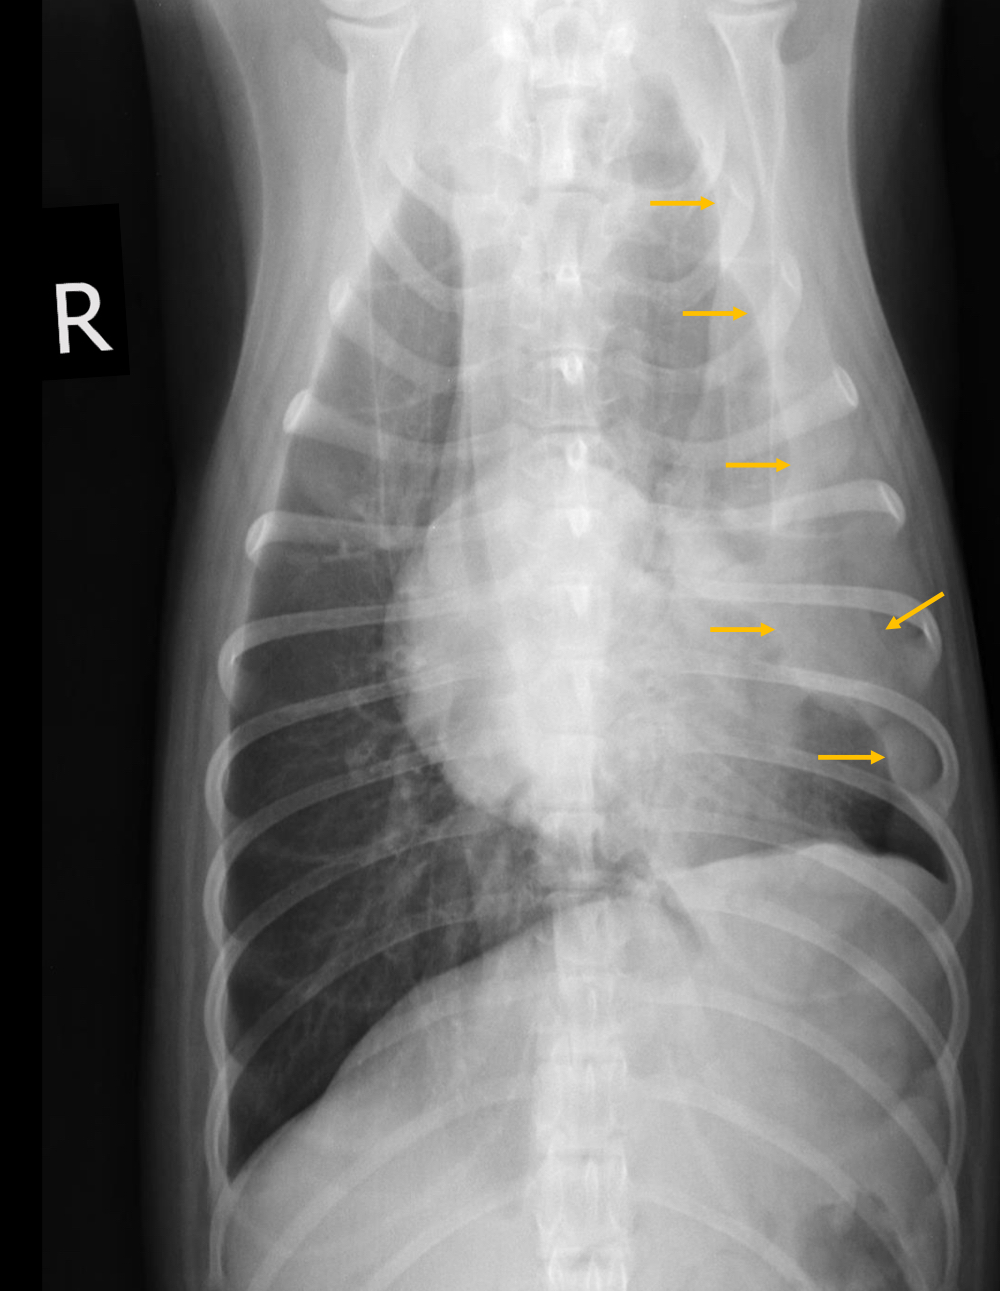

Q

What is likely happening in this radiograph?

A

• large soft tissue mass - opacity extends into thorax

• rib lesions

• mass displaces cardiac silhouette to the left